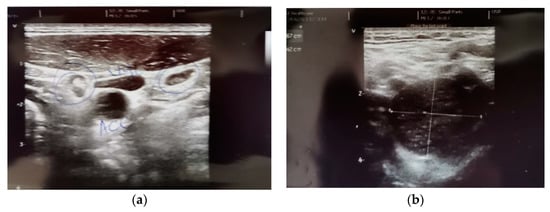

- The description, in all of the imaging investigations carried out initially, but also in the reassessment of the treatment, of a left latero-cervical adenopathy, stages II-III, with dimensional progression under treatment with BRAF/MEK inhibitors and Nivolumab—histopathologically and immunohistochemically invalidated during the surgical verification—schwannoma;